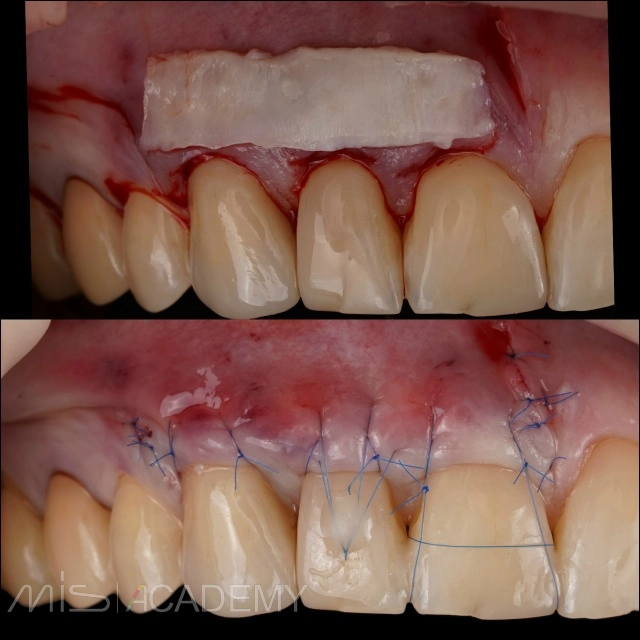

Пациент обратился с рецессиями в области 11, 12, 13 зубов. Тонкий биотип, оголённые корни, дискомфорт. Мы выполнили закрытие рецессий через VISTA доступ, микрохирургично и максимально щадяще.

— С сохранением кровоснабжения.

— Минимальная травматизация.

— Стабильный эстетический результат.